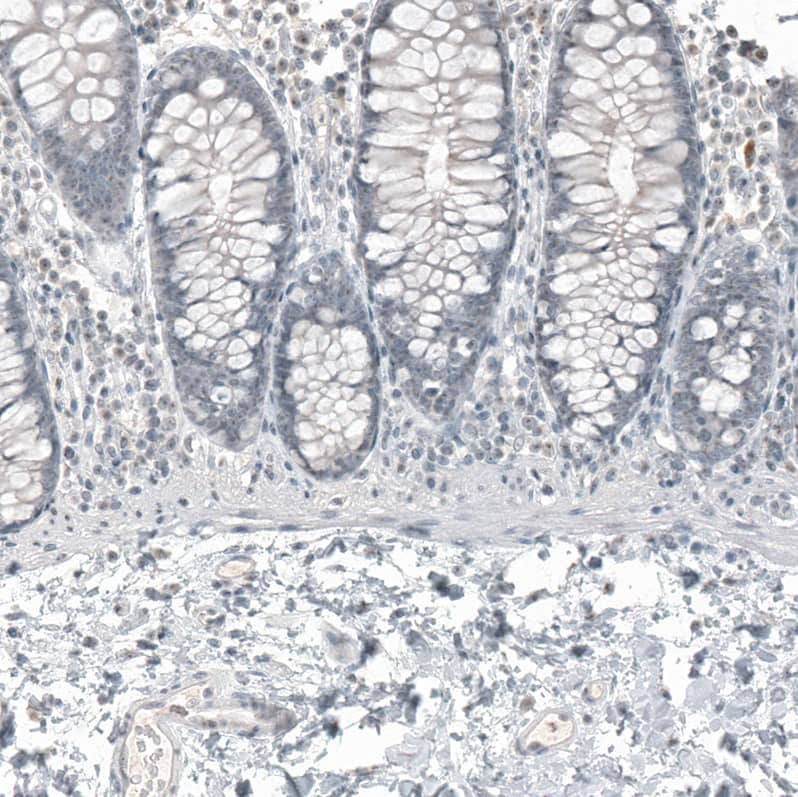

Staining of human fallopian tube shows moderate nuclear positivity in stromal cells.